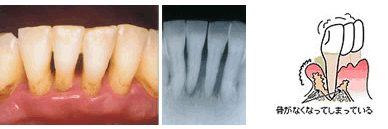

進行した歯周炎

支える骨がなくなると・・・

歯がグラグラ動き出すと、歯を抜くことになるかもしれません。

ここまで進行しても自覚症状がないのが歯周病の怖いところです |